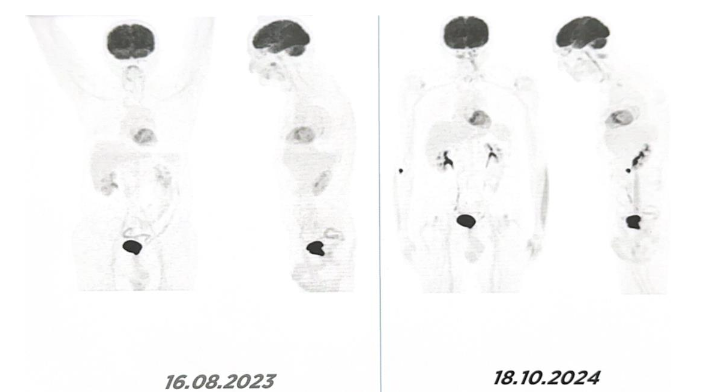

Since completing definitive therapy, the patient has been monitored annually with whole-body PET/CT.

To date, there is no evidence of recurrence of either the primary pulmonary adenocarcinoma or the secondary bladder carcinoma. More than 10 years after initial diagnosis, the patient remains clinically stable and continues maintenance therapy with Erlotinib (150 mg/day). Annual whole-body PET/CT imaging continues to demonstrate complete remission with no evidence of disease recurrence or progression.